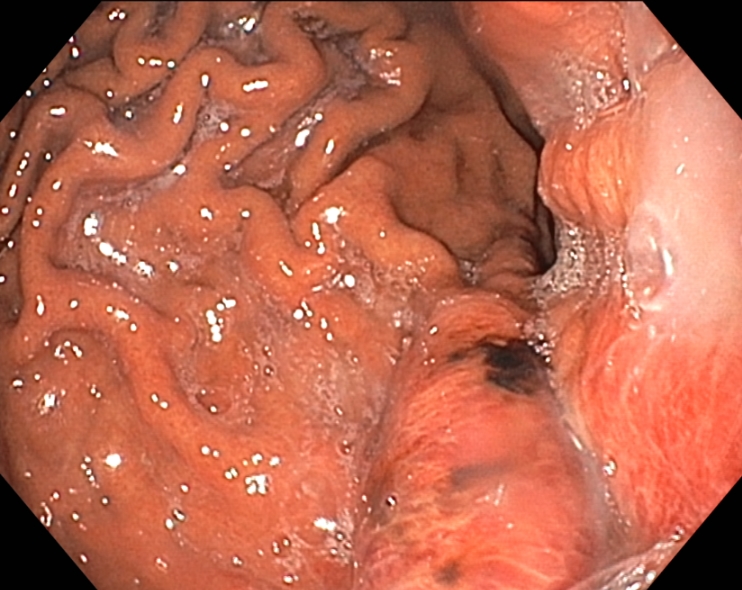

다음은 위내시경에서 확인된 위분문부와 유문부 점막에 생긴 급성위점막병변 사진입니다.